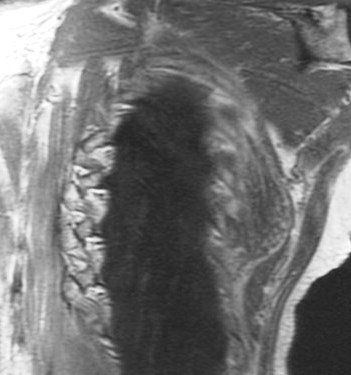

70 yo with 3 year history of slow growing mass in scapular region.

Typical location and dark appearance of this psuedotumor. Reference article.

Elastofibroma dorsi